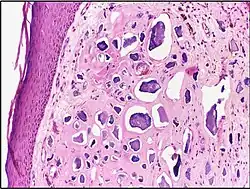

![]() | Cystic hyperplasia of endometrium | Micrograph showing cystic hyperplasia of endometrium. Cystically dialated glands are lined by proliferative type of epithelium. Stroma also resembles proliferative phase. No atypia is seen in the cells. | Category: Histopathology of hyperplasia endometrium | Cystic hyperplasia |